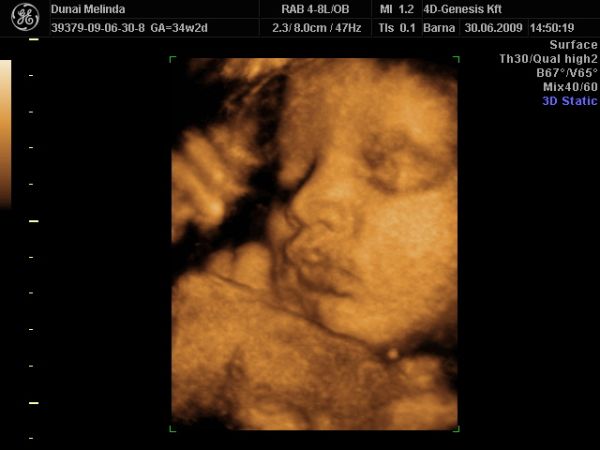

most elvileg megint vagy 10 hétig nem nézik Bogyót, 28-30. héten van megint kötelező UH. Iktass be közte egy 4D-t, ha tudsz. Én továbbra is javaslom a 4D Genesis-t, mi kedden megyünk másodjára. Olyan kedves az a nő, annyi mindent megnéz, nem csak a baba állapotát, hanem a tied is, és tuti nem enged úgy el, hogy ne hozza valahogy össze, hogy megkukkoljátok a lába közét, ha szeretnéd.

Hazajöttünk a nyaralásból, pont most, mikor kezd jó idő lenni, de előtte Pesten beugrottunk UH-ra a 4D Genesisbe. "Pici" fiam már 2992g, hát egyrészt örülök, minden ok, szépen visszafordult fejvégűbe, és a néni szerint ekkora méretekkel már esélye nincs visszafordulni. Másrészt meg kicsit aggódom, hogy hogy fog ez a gyerek kiférni????? Lilinek születésekor 35 cm volt a haskörfogata, Levinek már most 33,5. Akkora tokája van, hogy csak na!!! Meg 0,86 cm-es haja.:-)

Teszek pár képet....jópárat :lol: